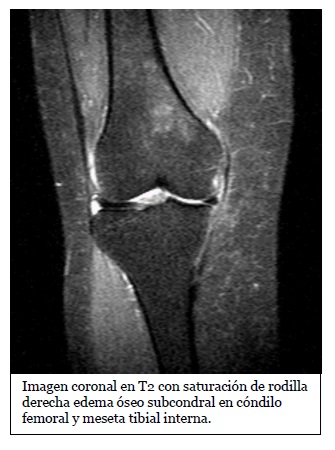

Imagen coronal de secuencia potenciada en T2 con saturación grasa de la rodilla derecha en paciente con lesión por traumatismo en valgo. Edema óseo en la

Fuente: https://epos.myesr.org/posterimage/esr/seram2014/124014/mediagallery/577012